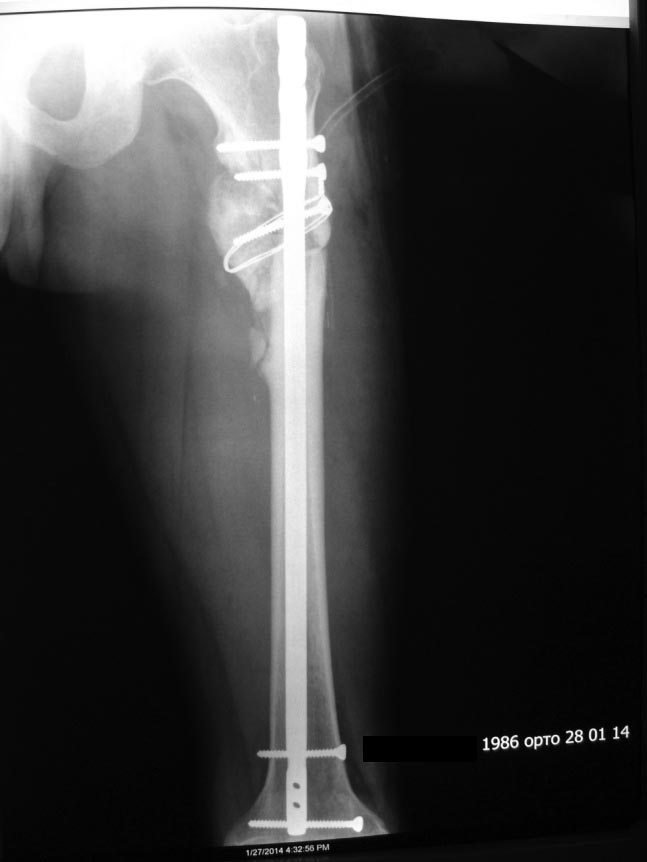

Уважаемые коллеги! Предоставляем один свежих случаев, если что то не так просим строго не судить! С уважением Ерсин Жунусов

... Вы, конечно, сделали гораздо лучше, чем было до операции. Просто несоблюдение 1-го правила остеотомий (а следом и 2-го) и привели именно к подобному расположению гвоздя и к остаточной деформации. + не вполне ясен подобный вариант блокирования проксимального фрагмента.

Отправитель: Lev Lapidus 21 Май 2014, 05:57

Извините, но здесь нет удлинения. Просто восстановлена прежняя длина бедра.